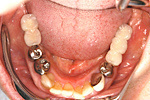

症例 11

① 左右の奥歯がありません。普通では左右つながった取り外しの入れ歯しか入りません。

② インプラントで固定式の義歯ができました。自分の歯に近い感じで食事ができます。

60才代 女性

総額:182万円(税別)

治療期間:6ヵ月

リスク副作用:メインテナンス不良ですと歯周炎、インプラント周囲炎になります。セラミックが欠けることがあります。